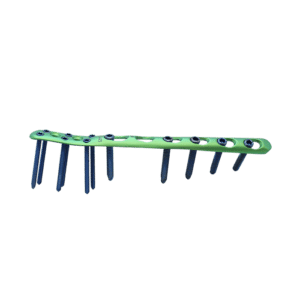

SISTEMA AIMIMINI VAL PARA MANOS 1.5/2.4/2.7 BLOQUEADO

El implante AIMIMINI val hand mini lock system se puede utilizar para la fijación temporal, corrección o estabilización del bloque óseo en la posición anatómica de la mano.